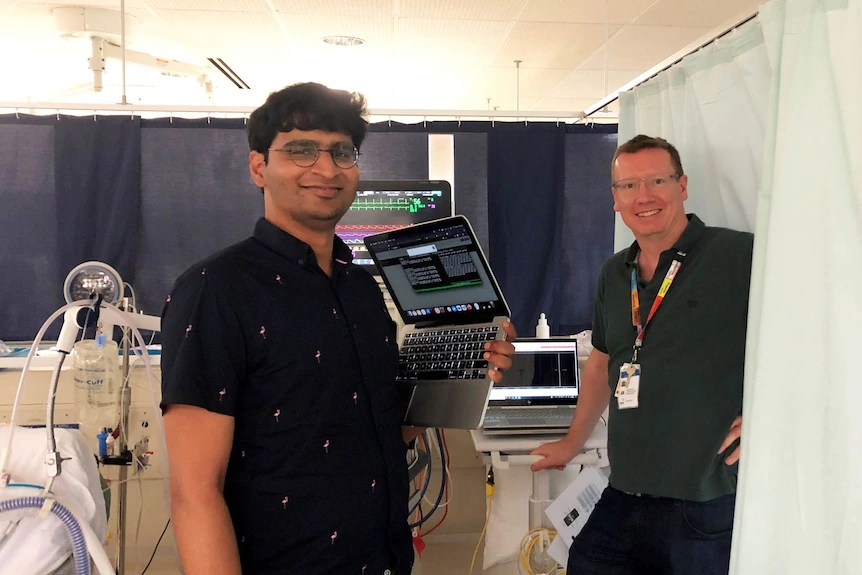

Pero recientemente un equipo médico de Australia logró desarrollar un algoritmo para predecir cuando el paciente experimentará una hemorragia cerebral. Esto le da a los médicos hasta 20 minutos antes para intervenir.

Investigadores del Royal Perth Hospital, Alfred Hospital y Royal Melbourne Hospital se unieron para desarrollar un algoritmo único en su tipo que puede predecir cuando un paciente se enfrentará a una hemorragia cerebral inminente.

Pero no crean que lograr esto fue sencillo. Se usaron más de 40 mil horas de datos de pacientes para crearlo y ahora el personal médico tiene hasta 20 minutos de ventaja para intervenir en el paciente.

Los médicos de los hospitales participantes afirman que esos minutos que tienen de ventaja pueden ser la diferencia entre la vida y la muerte.

Ahora trabajan en perfeccionar el algoritmo para que eventualmente pueda ser usado en hospitales de Australia, contribuyendo a salvar vidas. Este avance es importantísimo.